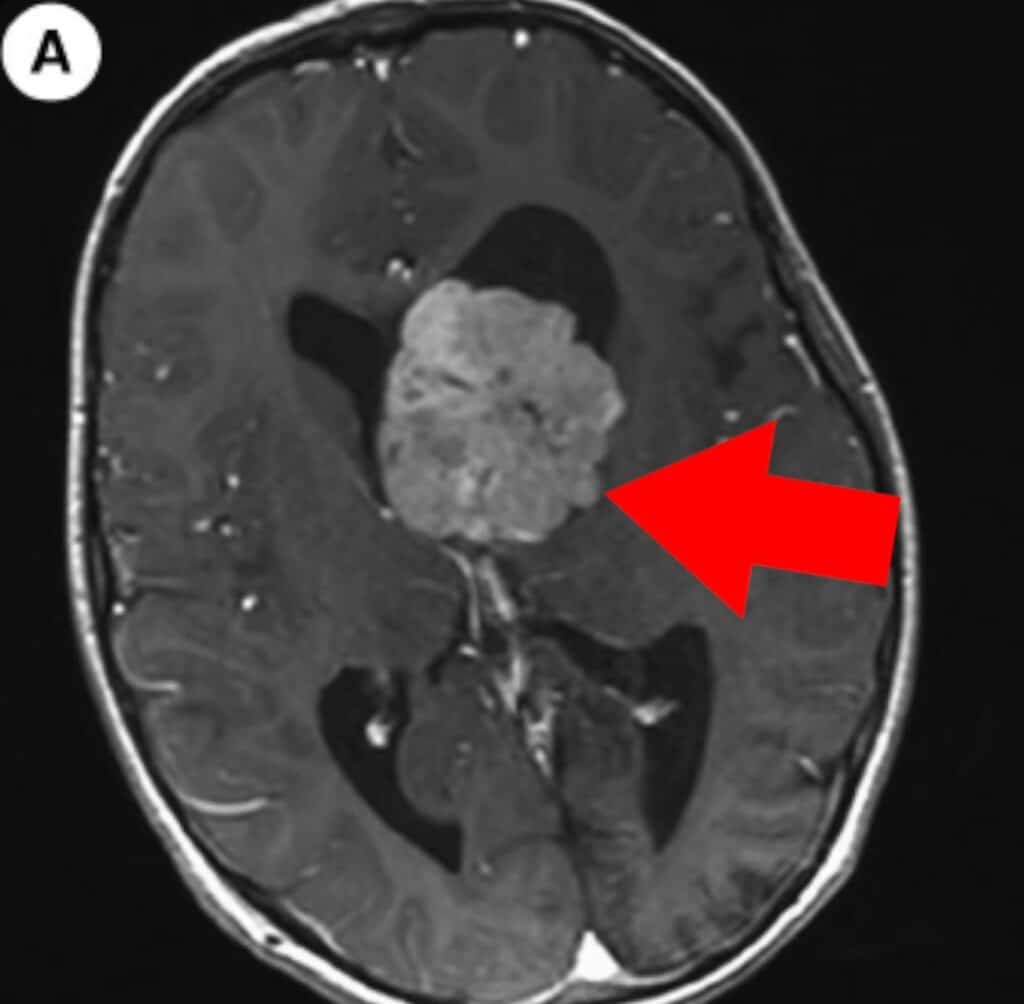

Useimmissa kudoksissa tämä ei ole heti kohtalokasta. Mutta aivoissa tilanne on kriittinen, koska:

- aivot ovat suljettuna kallon sisällä

- aivot puristuvat kalloa vasten

- verenkierto heikkenee

- syntyy hapenpuute

- kudos alkaa vaurioitua

Tämä voi johtaa pahimmissa tapauksissa pysyvään aivovaurioon tai kuolemaan.